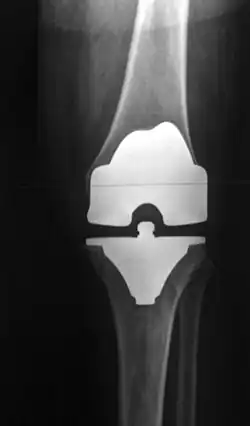

Kunstgewrichten worden toegepast voor heupen, knieën, schouders,ellebogen enkels en polsen.

Kunstheupen zijn zeer succesvol, gevolgd door knieën, maar ook vervangende kunstschouders, -enkels en -polsen winnen terrein. In de rug worden ook versleten of beschadigde (tussen)wervelschijven meer en meer vervangen, maar door de vele zenuwbanen en dergelijke is dat niet zonder risico.